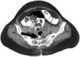

Rectal perforation

Rectal foreign bodies are large foreign items found in the rectum that can be assumed to have been inserted through the anus, rather than reaching the rectum via the mouth and gastrointestinal tract. It can be of clinical relevance if the patient cannot remove it the way they intended. [Source: Wikipedia ]